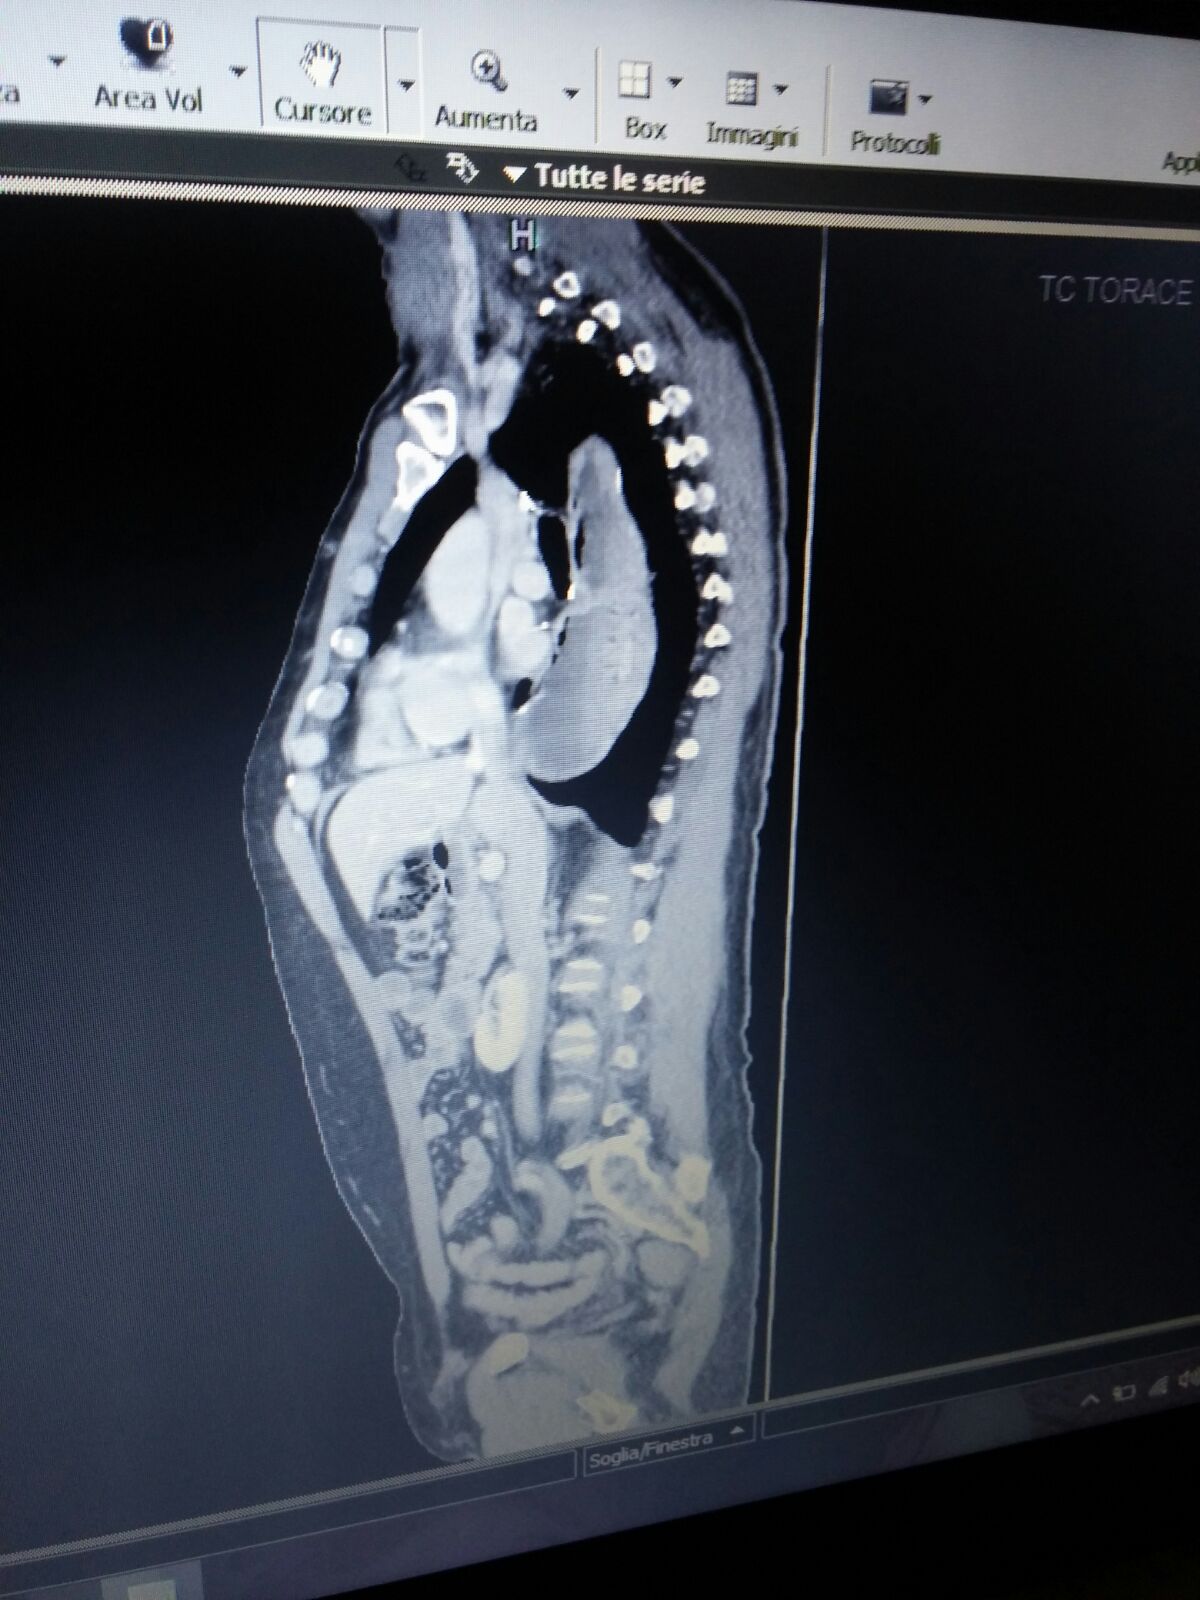

Commento file: Luglio 2014: prima dell'intervento ernia

Immagine3.jpg

[ 221.56 KiB | Osservato 1028 volte ]